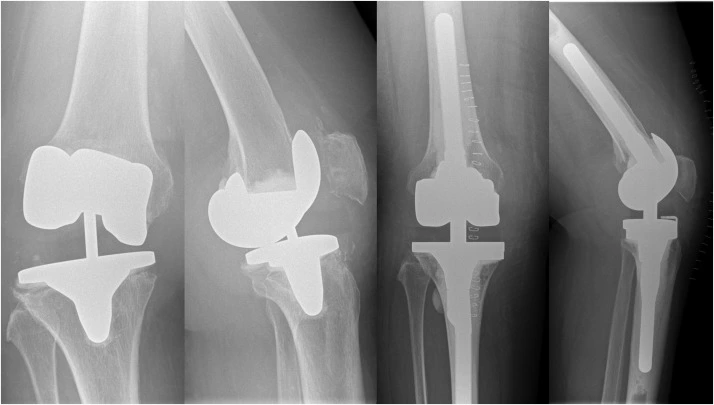

Revision Knee Replacement

What is Revision Knee Replacement?

Revision knee replacement is a specialized surgical procedure performed when a previous knee implant has worn out, loosened, or developed complications such as infection or instability. Unlike a primary knee replacement, revision surgery is more complex and requires experienced orthopedic surgeons, advanced planning, and high-quality implants—everything we offer at Numed Hospital.

4. Precise Placement of the New Implant – A high-quality revision knee implant is used for better durability and function.